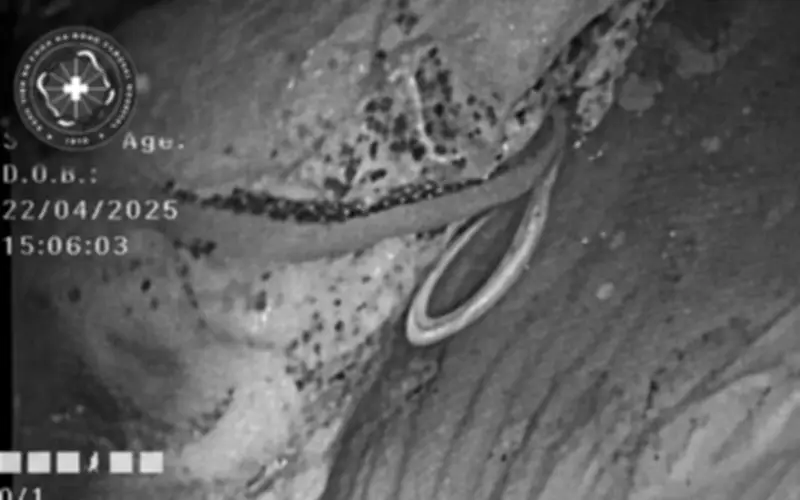

Mới đây, bệnh nhân N.T.H. (47 tuổi) nhập Bệnh viện Đa khoa Hà Đông trong tình trạng đầy bụng, khó tiêu kéo dài, kèm rối loạn đại tiện và mệt mỏi không rõ nguyên nhân. Trong quá trình nội soi đại tràng, bác sĩ chuyên khoa II Nguyễn Hợp, phụ trách Trung tâm Nội soi, bất ngờ phát hiện một hình ảnh bất thường: một ký sinh trùng dạng sợi trắng, dài, đang cuộn trong lòng ruột. Đây được xác định là nguyên nhân trực tiếp gây ra các triệu chứng kéo dài ở bệnh nhân.

“Không phải mọi rối loạn tiêu hóa đều xuất phát từ viêm dạ dày hay rối loạn chức năng. Trong một số trường hợp, nguyên nhân rất cụ thể và có thể điều trị dứt điểm nếu được phát hiện sớm”, bác sĩ cho biết.

Ngay sau đó, các bác sĩ tiến hành đánh giá mức độ nhiễm, xác định loại ký sinh trùng và tình trạng tổn thương niêm mạc ruột. Bệnh nhân được chỉ định điều trị bằng các thuốc tẩy giun thông dụng như Albendazole hoặc Mebendazole, đồng thời được tư vấn kỹ về vệ sinh ăn uống, sinh hoạt nhằm hạn chế nguy cơ tái nhiễm.